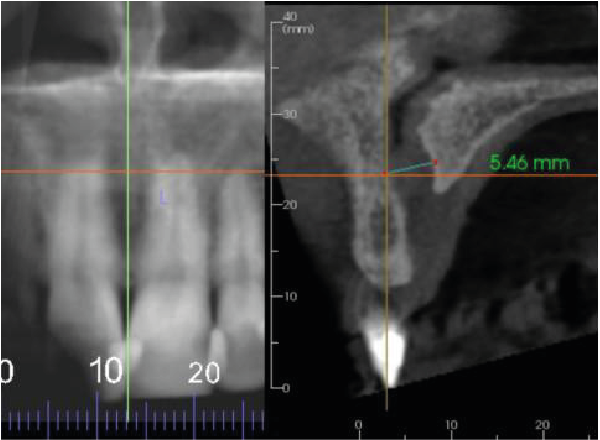

Image 3

The nasopalatine canal has a concave surface and the width is at the upper limit of normal (6mm). This may indicate the development of a nasopalatine cyst. Taking a periapical radiograph in 12 months is recommended to check for any enlargement (Image 3).